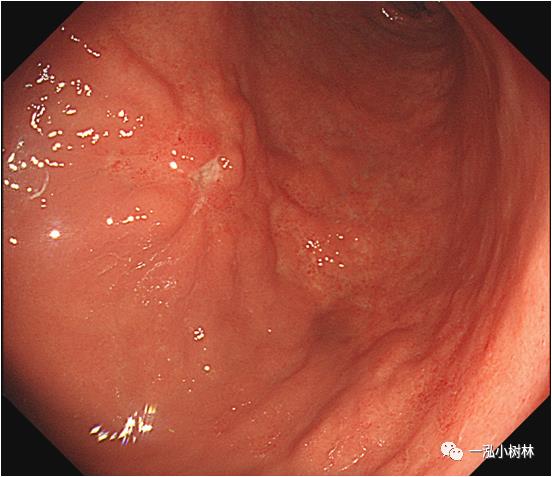

例2 胃窦病变

图2a 白光内镜:胃窦前壁高分化腺癌(Tub1)。